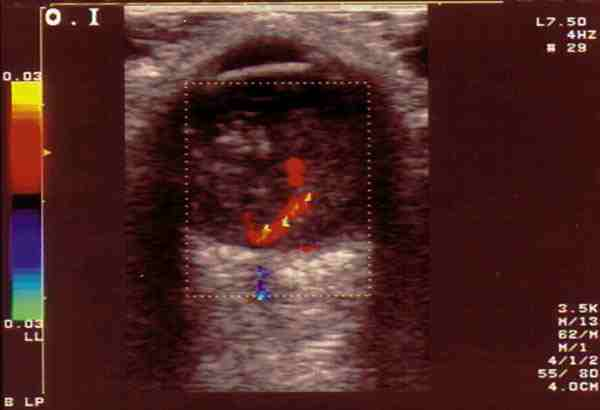

Figura 3. Retinoblastoma vascularizado mediante el doppler color se

observa el registro correspondiente a un vaso arterial.